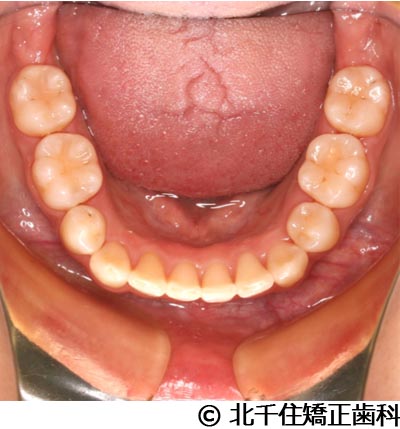

【症例3】叢生

- 治療前

- 治療後

- 治療名

- 叢生

- 費用

- 1,125,000円(税込)

- 期間

- 2年1ヵ月

- 治療回数

- 26回

- 通院頻度

- 1ヵ月ごと

- 年齢・性別

- 19歳3ヵ月・女性(初診時)

治療内容

-

患者様の症状

主訴:デコボコ、口元の突出

治療方法

上下顎第一小臼歯4本を抜歯してワイヤー矯正(セラミックブラケット)。

治療結果

叢生に対し抜歯を併用した矯正治療により、歯列および咬合関係の調整を行った症例である。治療後は保定装置を使用し、歯列および咬合の安定維持を目的として定期的な経過観察を行っている。

※治療結果は個人差があります。

治療を行う上での注意点(リスク・副作用)

歯磨き不良に伴うカリエスや歯周病、歯根吸収など。